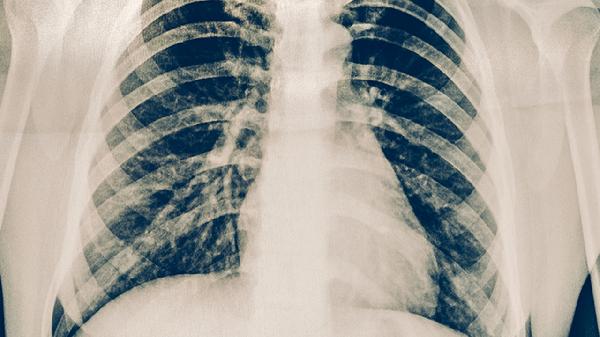

既往肋骨骨折史者,骨痂过度增生或错位愈合可能形成局部骨性突起。此类包块质地坚硬且固定不移动,可能伴有慢性钝痛。影像学检查可显示骨痂形态,若无神经压迫症状一般无须处理,疼痛明显者可服用布洛芬缓释胶囊、塞来昔布胶囊等非甾体抗炎药缓解。